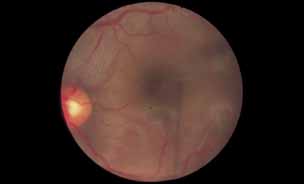

As an example, patients with posterior segment involvement by the spirochete Treponema pallidum may manifest visual loss on the basis of a large number of different mechanisms.16–21 These include perioptic neuritis, retinal periphlebitis or periarteritis, diffuse neuroretinitis, cystoid macular edema, or choroidal neovascularization. Fluorescein angiography may be helpful not only in establishing the causative agent but also in determining the predominant mechanism of visual loss (see Figs. 4 and 5).

Fig. 4 Luetic neuroretinitis. Color photograph showing placoid opacity at the level of the retinal pigment epithelium.